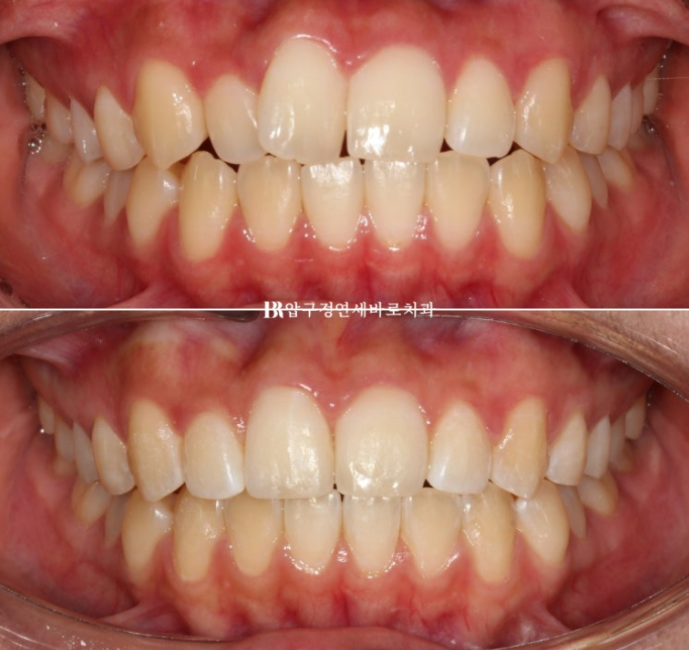

전 후 비교 보겠습니다.

토탈 치료기간은 6개월입니다.

23.12~24.06

심해보이는 덧니도 적절하게 치료한다면 의외로 짧고 간단하게 교정이 마무리가 됩니다.